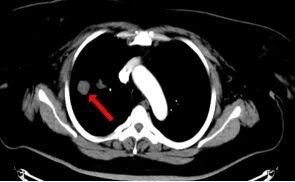

左肺下叶肿瘤 右肺下叶结节

患者许某,女性,41岁,因“骨盆软骨肉瘤术后2年,发现双肺多发结节”就诊。影像学检查提示,其双肺及胸膜下存在多发结节及肿块,尤其是左肺下叶一处病灶,位置特殊,紧邻上腔静脉及左心室等重要大血管结构。明确这些病灶的性质是决定后续治疗方案(包括是否适合重离子放疗等先进治疗)的关键,但常规穿刺路径风险极高,稍有不慎即可能引发出血等严重并发症。

2026年1月24日,在充分的术前准备和讨论后,手术正式开始。患者取俯卧位,采用负压垫进行体位固定,确保术中体位稳定。首先行增强CT扫描,精确勾画出靶病灶与周围血管的立体关系,规划出最优穿刺路径,避开重要结构,并在体表做好精准标识。在局部麻醉下,郭福新教授凭借娴熟的手法,在CT实时引导下,将活检针精准、平稳地经皮穿刺至预定靶点。术中多次扫描确认针尖位置无误,成功获取了高质量的组织标本。整个操作过程流畅,术中及术后即刻复查未见气胸、出血等并发症,实现了对高风险病灶的“毫米级”精准狙击。